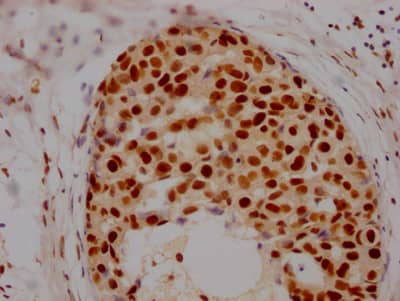

Immunohistochemistry: Histone Deacetylase 2/HDAC2 Antibody (9H4) [NBP3-26239] -

Immunohistochemistry: Histone Deacetylase 2/HDAC2 Antibody (9H4) [NBP3-26239] - Image of Histone Deacetylase 2/HDAC2 Antibody (9H4) diluted at 1:100 and staining in paraffin-embedded human breast cancer performed. After dewaxing and hydration, antigen retrieval was mediated by high pressure in a citrate buffer (pH 6.0). Section was blocked with 10% normal goat serum 30min at RT. Then primary antibody (1% BSA) was incubated at 4C overnight. The primary is detected by a Goat anti-rabbit IgG polymer labeled by HRP and visualized using 0.05% DAB.